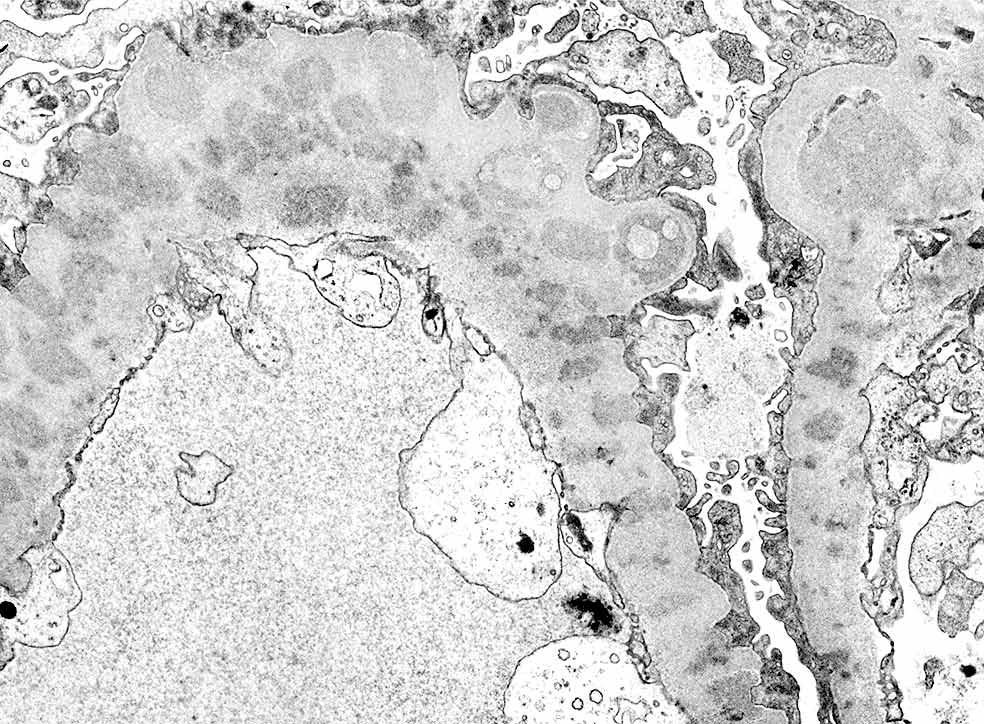

Pared capilar glomerular alterada por la presencia de depósitos electro densos en un caso de enfermedad glomerular por depósitos de inmunoglobulinas. Aumento 6.000X. Cortesía Dr. Luis F. Arias. Departamento de Patología.